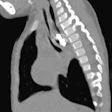

Case report: Button battery lodged in esophagus for a year